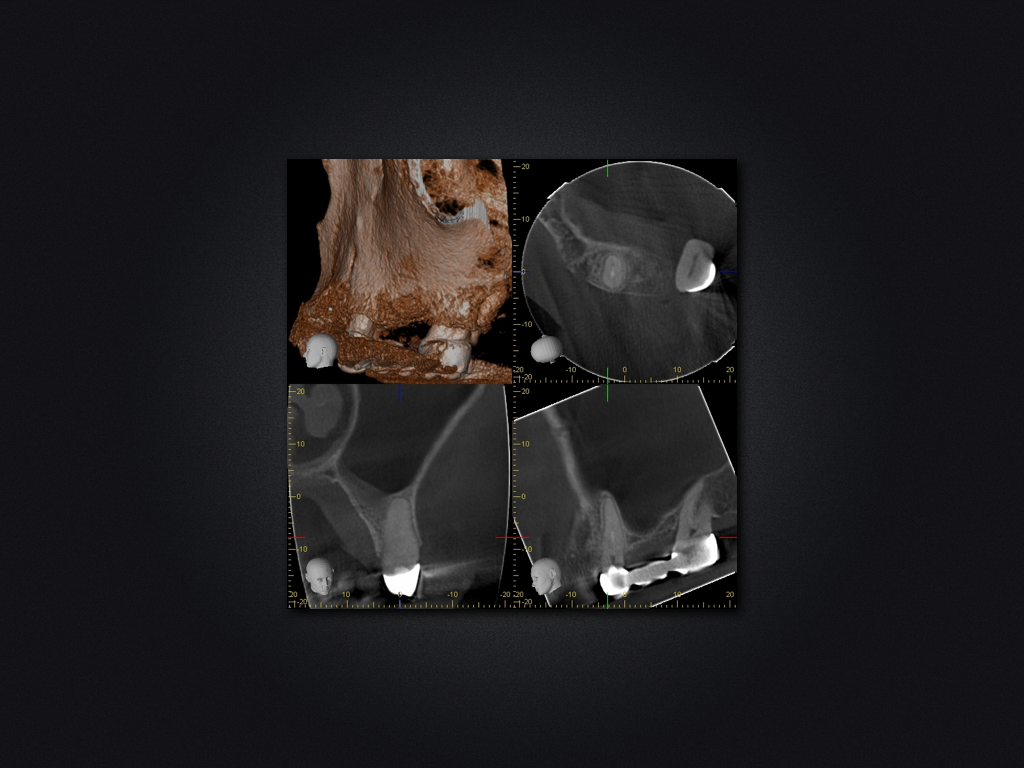

25D.004

Spülzwischenfall?